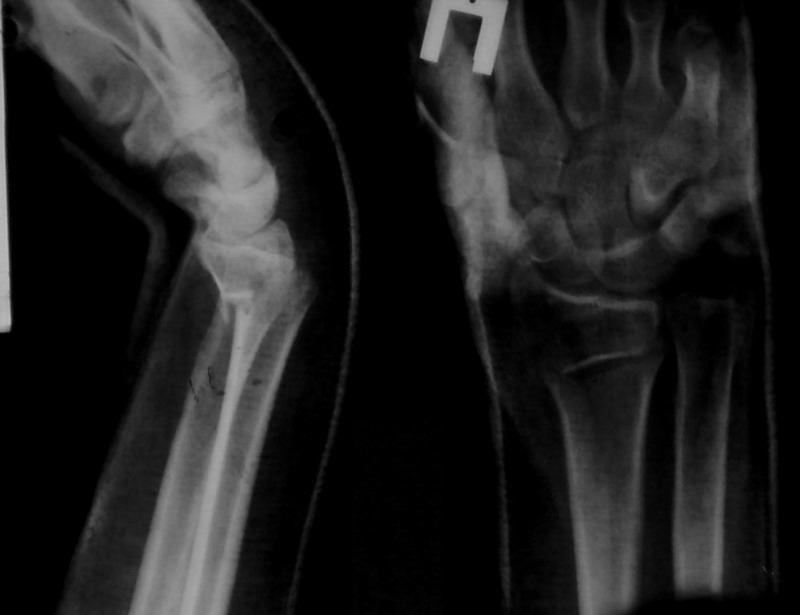

Sergey Melashenko 20 Декабрь 2007, 03:03

Сегодня контроль - все в порядке. Никакой неврологии нет.

Иногда многие вопросы можно решить грамотной репозицией. И не оперировать так часто, как сейчас.

Не сильно ли мы увлекаемся остеосинтезами... ? Как говорили корифеи, лучашая операция та , которую не сделали.